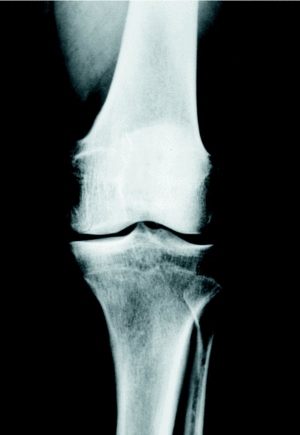

Figura 3. Corrección quirúrgica del caso mostrado en la figura 2. Se utilizó la placa T3, que proporcionó un montaje estable después de la osteotomía, añadiéndose un tornillo de compresión para mayor solidez. La corrección fue de 8o de valgo; la consolidación se obtuvo a las 9 semanas. La imagen corresponde al control a los tres años.

La consolidación de la osteotomía tibial se logró a las 9,7 +/ 1,25 semanas (mínimo: 8; máximo: 12) (figs. 2 y 3). En el postoperatorio inmediato se presentaron 6 complicaciones. En 4 pacientes existió una paresia transitoria del ciático poplíteo externo que se recuperó en todos ellos a las 9 semanas de media. Hubo un caso de infección superficial, que curó con tratamiento antibioterápico oral y curas tópicas; y un caso de fractura de platillo tibial interno por osteotomía insuficiente, que condicionó un mal resultado (fig. 4). A medio plazo hubo dos pacientes que precisaron la retirada de la placa por molestias atribuidas a la protrusión subcutánea del material.

El seguimiento radiológico final demostró una corrección del eje de la extremidad que pasó a ser de 8o de valgo (desviación estándar [DE]: 2,2) (mínimo: 5; máximo: 12). No hubo cambios entre la corrección apreciada en el postoperatorio y la final, no progresó la usura ni el pinzamiento de la interlínea interna, ni evolucionó la artrosis en los otros compartimentos. Los resultados de la evolución clínica y radiológica al final del seguimiento se muestran en la tabla 1.